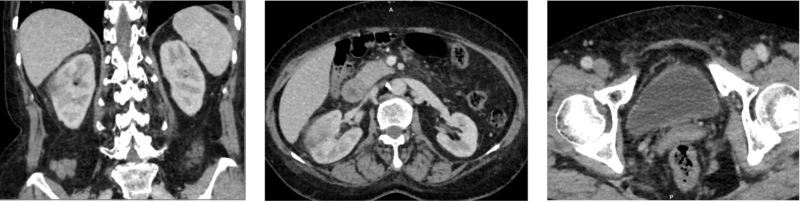

Hình ảnh theo dõi viêm thận bể thận bên phải trên MRI

Siêu âm ổ bụng phát hiện nốt vôi hóa gan phải và nang thận phải. Trên phim chụp CT có tiêm thuốc cản quang, ghi nhận hình ảnh gợi ý viêm thận – bể thận phải, kèm nang thận phải.